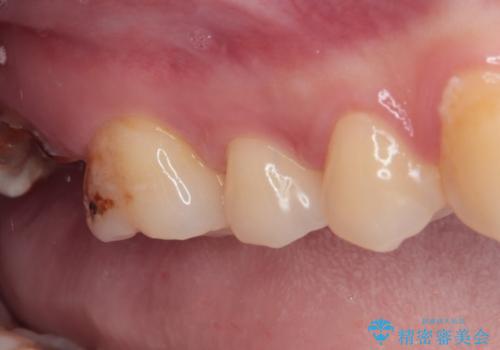

- 過去の歯医者通いの恐怖から虫歯を放置してきたものの、一大決心して来院された患者様です。

神経組織の失活している歯や歯根だけが残っている歯などがあり、全体的に歯石も多く付着している状態でした。

まずは歯石除去とブラッシング方法などの衛生指導を徹底的に行って口腔内環境を改善し、汚れの溜まりやすくなっている親知らずは全て抜去することとしました。

その後、歯根だけとなっている歯はインプラントに、神経組織の失活している歯は根管治療を行い、いずれもオールセラミッククラウンにて補綴治療を行うこととしました。

右上のインプラント治療は、1DAYインプラント治療(抜歯即時埋入・即時荷重)の適応となりましたので、通常3回必要な外科処置の回数を1回に集約させることができました。